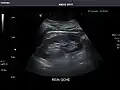

Liver

Ultrasonography of the liver with some standard measurements[6]

In patients with deranged liver function tests, ultrasound may show increased liver size (hepatomegaly), increased reflectiveness (which might, for example, indicate cholestasis), gallbladder or bile duct diseases, or a tumor in the liver.